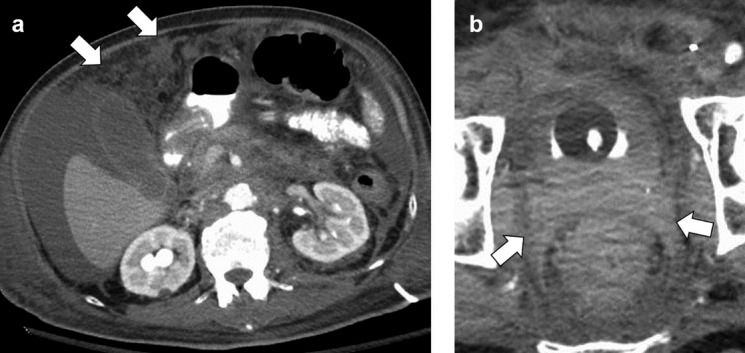

- On CT / MRI, PUC case series demonstrated focal bladder mass in 68% of cases and diffuse mural thickening in 32% of cases (Can Urol Assoc J 2017;11:E50)

- On CT / MRI, imaging specific to PUC compared with conventional UC may be discontinuous thick sheets of tissue extending along fascial pelvic planes (Can Urol Assoc J 2017;11:E50)

Radiology images